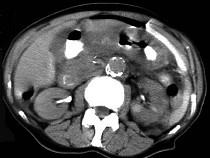

问题 男,44岁,突然中上腹痛,压痛,反跳痛,腹肌紧张,发热,白细胞计数升高,CT检查如图,最可能诊断是 ( )

选项 A.急性胰腺炎 B.慢性胰腺炎 C.胃小弯溃疡穿孔 D.胰腺癌 E.胃癌

答案 C